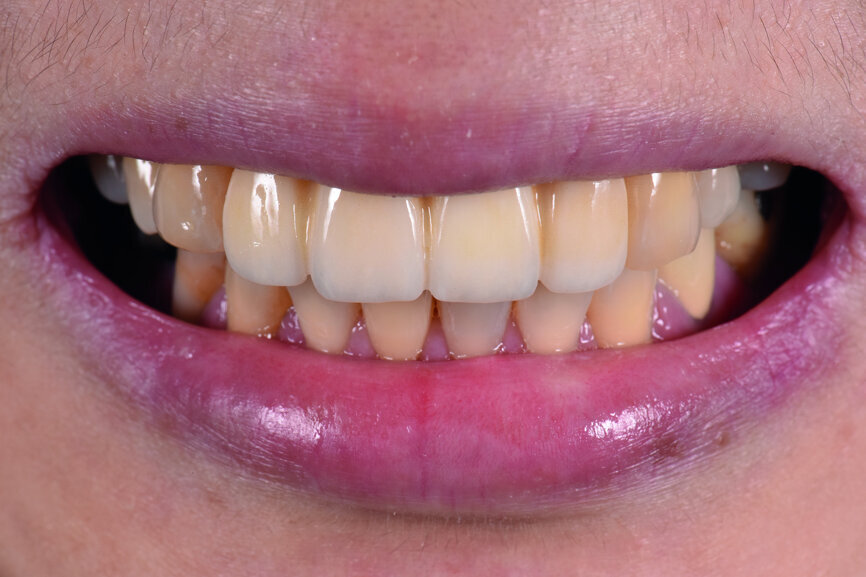

The aesthetic and functional outcomes of the provisional restoration were checked. The tip of tooth #13 was too low to achieve a good smile line. When checking the intercuspal position (ICP) and lateral excursion using 80 μm occluding paper, tooth #13 was found to be out of contact. After reshaping the labial contour and filling the lingual surface with resin, tooth #13 had good contact and guidance during ICP and lateral excursion (Figs. 19–23).

Fig. 19: The patient smiling with the provisional restoration in situ.

Fig. 20: The patient smiling

after adjustment of the labial contour of tooth #13.